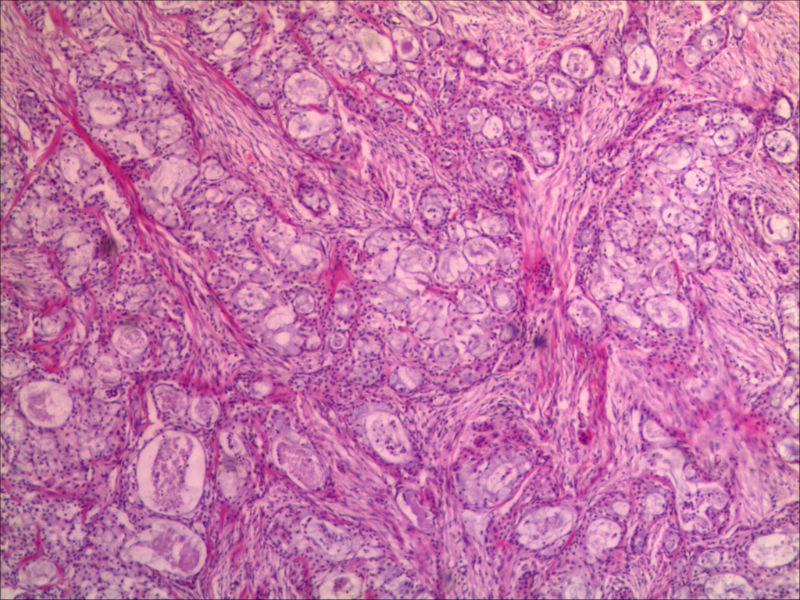

右下颌肿物女26岁 大家帮帮看看

典型的黏液表皮样癌,低度恶性。

本例可以看到典型的产粘液细胞、鳞状细胞、中间细胞和透明细胞,因为产粘液细胞多,甚至形成粘液湖,加之包块似有包膜,分界清楚,应该考虑粘液表皮样癌(低度恶性)。